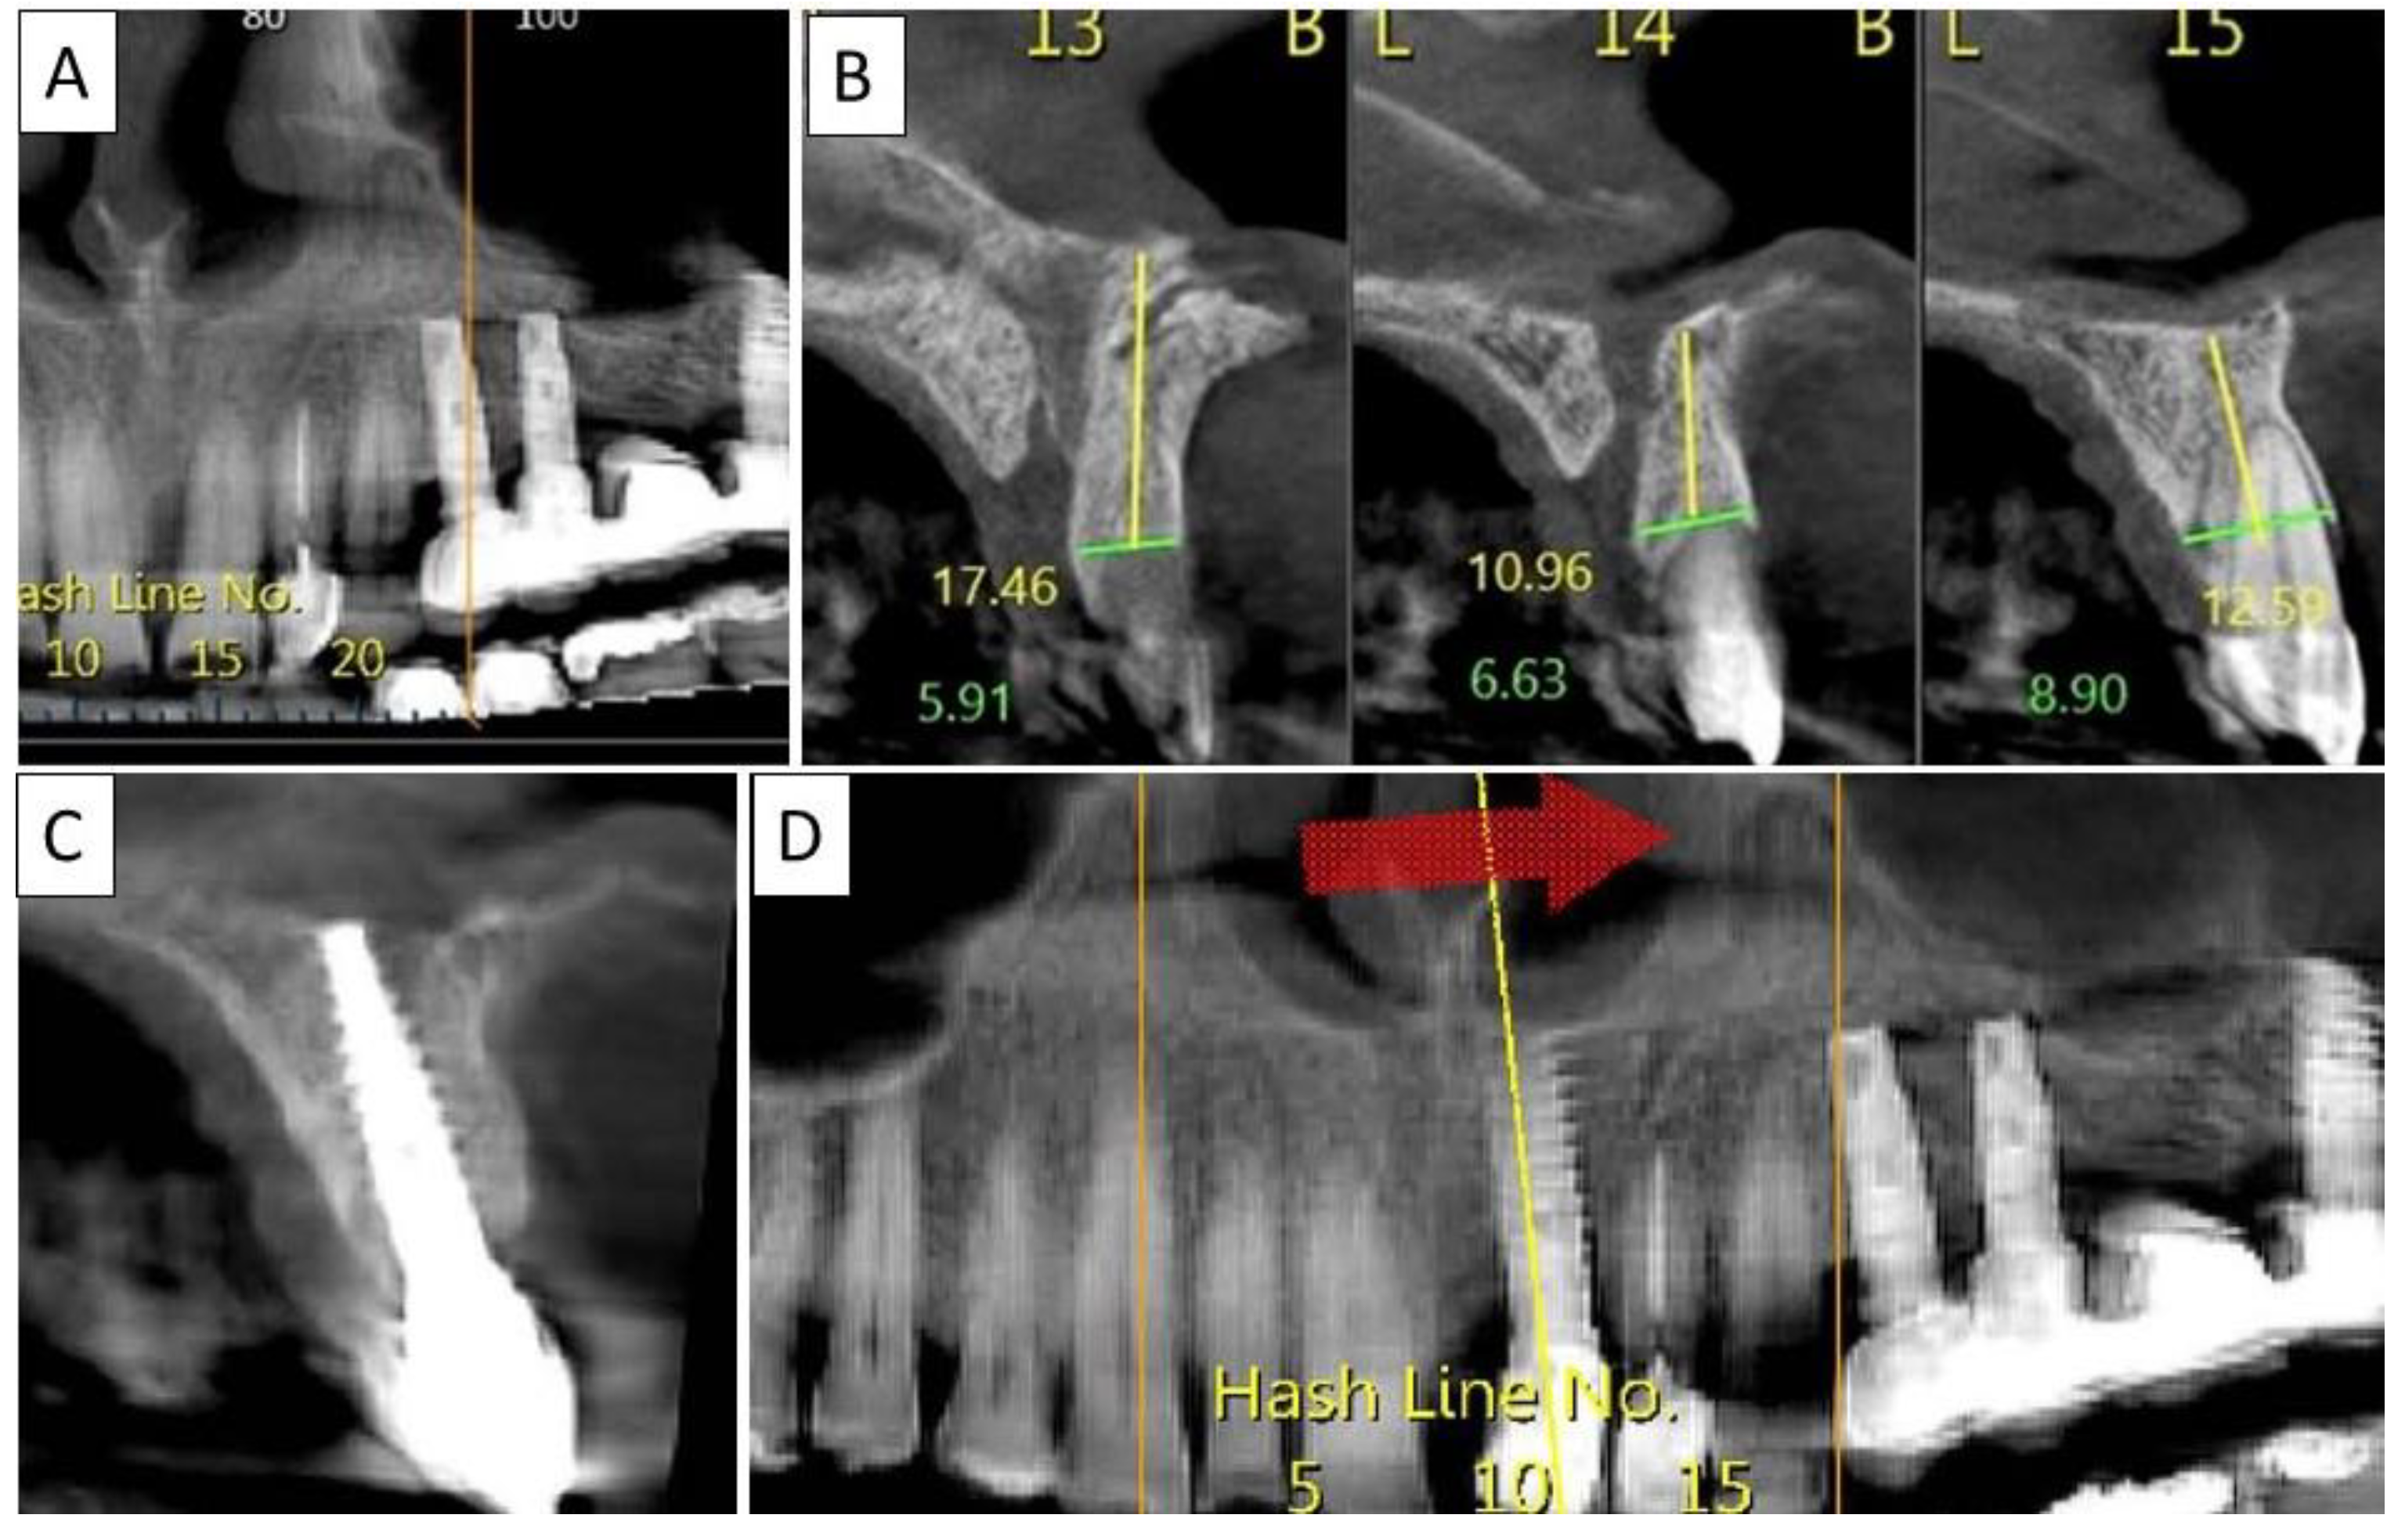

Figure 7.

(A) Panoramic CBCT section shows bone loss around tooth 21. (B) Sagittal CBCT section of the area around tooth 21 shows extensive buccal bone loss. (C) A sagittal CBCT section shows the implant placed at site 21 with a restored cortical buccal plate. (D) Panoramic CBCT section shows bone formation around the implant in area 21.